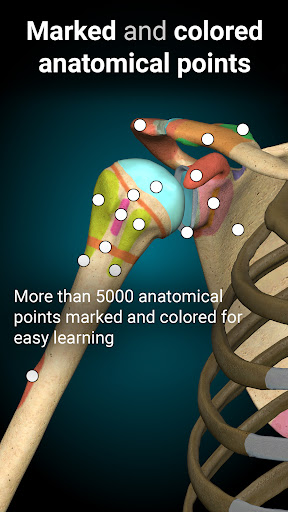

A true and totally 3D app for studying human anatomy, built on an advanced interactive 3D touch interface.

★ 3D location quizzes to test your knowledge